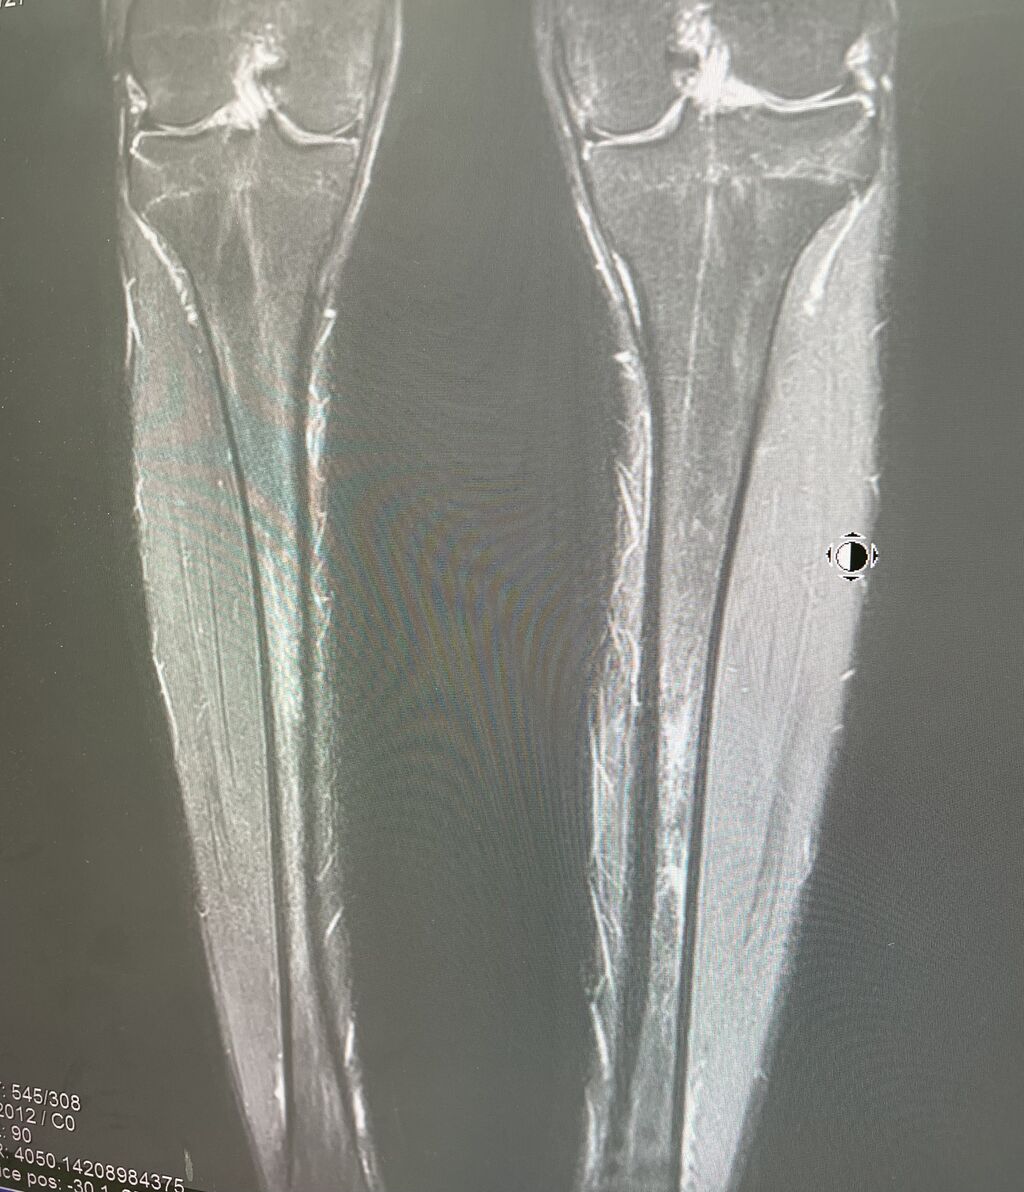

箱根駅伝、区間賞に 輝いた選手

足の相談です

MRIで、診察した後、

筋肉をほぐしテーピング指導し

徐々に復活さしていい行く予定です